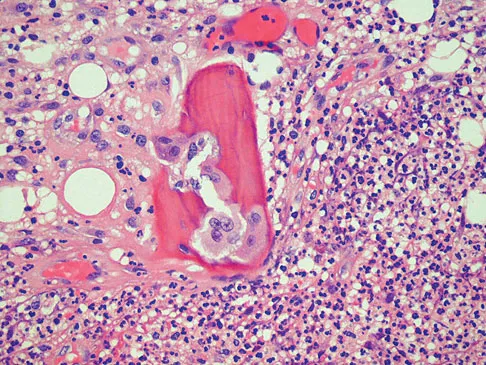

A 30-year-old woman has pain in her right hand. The radiograph, CT scan, and biopsy specimen are seen in Figures 38a through 38c. What is the most likely diagnosis?

Explanation